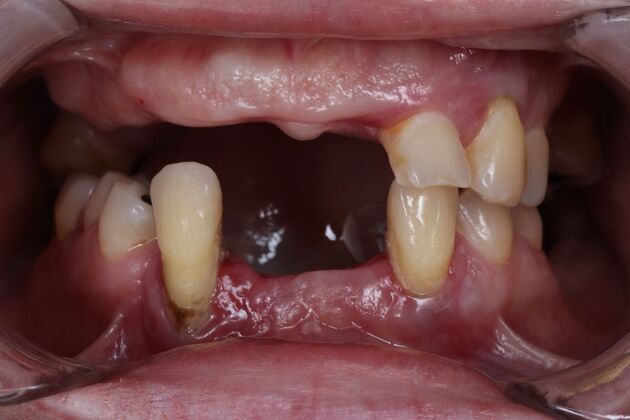

Dental Implants: Silvia - Fixed Hybrid denture

Description

In Silvia's case, the use of a removable denture that didn't fit well leave her with low self-esteem and not wanting to smile. In her case, after analyzing her profile, we have created a total fixed prosthesis to achieve a natural and harmonious smile. Today dentistry often restores not only oral health, but the general health of the patient.